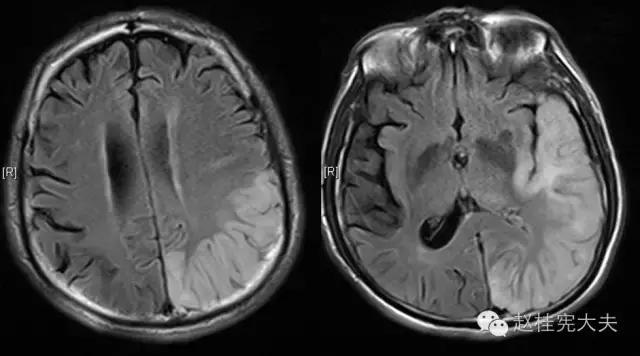

当看到磁共振片子的时候,我知道,我们忽略了一些东西......

患者的磁共振影像不符合脑血管病的血供分布,跨了大脑中动脉和大脑后动脉范围,且病灶偏皮层分布。大脑前、中、后动脉血供分布(横断面)见下图

这不是一个真的“脑卒中”,而是一个“卒中样发作”。

上周,于发病后2月复查磁共振:

到此为止,MELAS的诊断应该在没有基因确诊的情况下在临床上得到认可了,患者明确诊断为线粒体脑肌病伴乳酸血症和卒中样发作(MELAS),解释了患者的所有症状,患者母亲不明原因地死亡也得以真相大白,患者的相关亲属们在未来的人生路上也多了一份呵护......